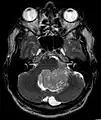

Épendymomes de la fosse postérieure

Les épendymomes localisés dans la fosse postérieure (PF) sont des tumeurs radiologiquement homogènes et bien délimitées, avec des remaniements hémorragiques et d'éventuelles taches de calcification montrant une prise de contraste variable due à la nécrose et à la formation de kystes. Ces tumeurs peuvent être localisées à l'intérieur du quatrième ventricule avec une expansion latérale possible à travers les foramens de Luschka ou le foramen de Magendie. Les épendymomes PF peuvent être divisés en deux sous-groupes en fonction de leur profil épigénétique : les PF de groupe A (PFA) et les PF de groupe B (PFB) [11].